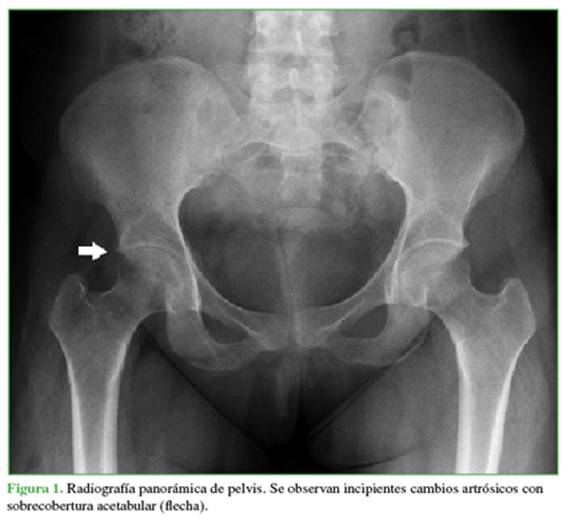

Se solicitan radiografías panorámica de pelvis (Figura 1) y de cadera derecha, de frente (Figura 2).

Las radiografías panorámica de pelvis y de cadera derecha, de frente muestran incipientes cambios artrósicos con mínima sobrecobertura acetabular. No se visualizan lesiones líticas ni blásticas.